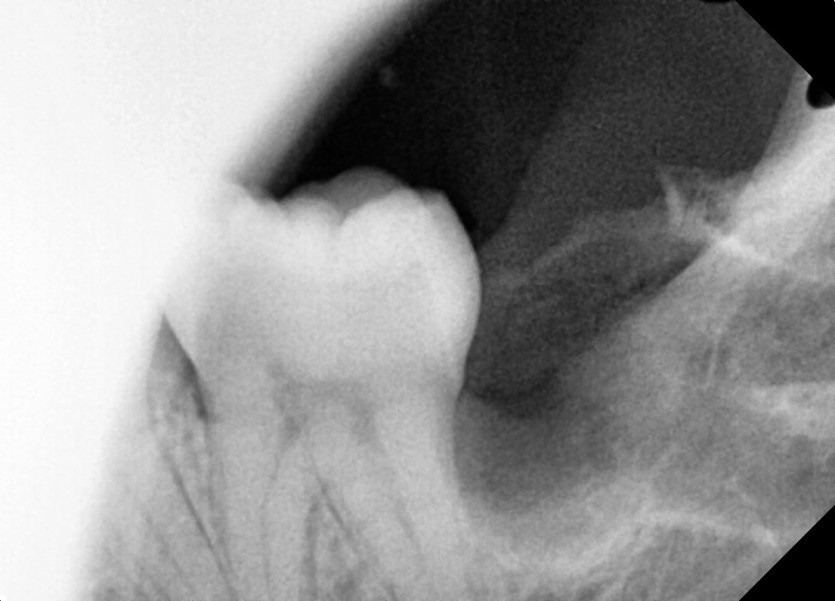

#38 사랑니 발치

구강 외과 전문의가 당일 발치했습니다.